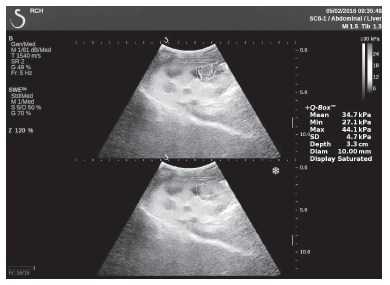

Клинический пример из первой группы. Пациент М., с хронической почечной недостаточностью. Трансплантация почки произведена от живого родственного донора. Трансплантат находится в правой подвздошной области. При нормальном функциональном состоянии трансплантата, показатели цветовой и спектральной допплерографии оценивались как удовлетворительные, с индексом резистентности не более 0,60 (рис. 1); показатели жесткости паренхимы почечного трансплантата при УЭСВ на различных участках составили от 20,05 до 29,18 кПа (рис. 2-4).

Рисунок 3. Исследование в режиме ультразвуковой эластографии сдвиговой волны у пациента М.: жесткость паренхимы в зоне верхнего полюса почечного трансплантата 21,4 кПа

Клинический пример из второй группы. Пациент К. перенес операцию пересадки почки от живого родственного донора. Трансплантат в левой подвздошной области. Индекс резистентности в междольковых артериях составил 0,70 (рис. 5). В сегментарных артериях индекс резистентности составил 0,66 (рис. 6). Показатели жесткости паренхимы почечного трансплантата при режиме УЭСВ составили от 31,6 до 36,9 кПа (рис. 7-9).

Рисунок 8. Исследование в режиме ультразвуковой эластографии сдвиговой волны у пациента К.: жесткость паренхимы в зоне нижнего полюса почечного трансплантата 34,7 кПа